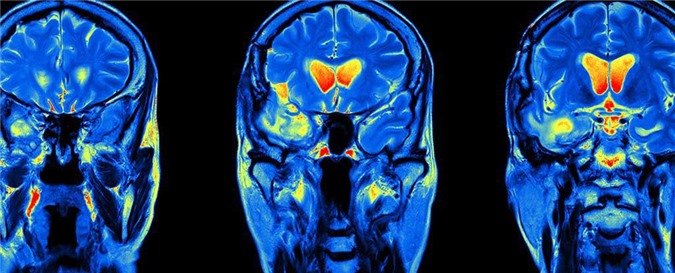

Xuất hiện tia hy vọng mới trong lĩnh vực chữa trị bệnh ung thư não khi các nhà khoa học vô tình nhận ra được hiệu quả bất ngờ trong việc hỗ trợ tiêu diệt khối u của một loại thuốc chuyên dùng để điều trị… sốt rét.